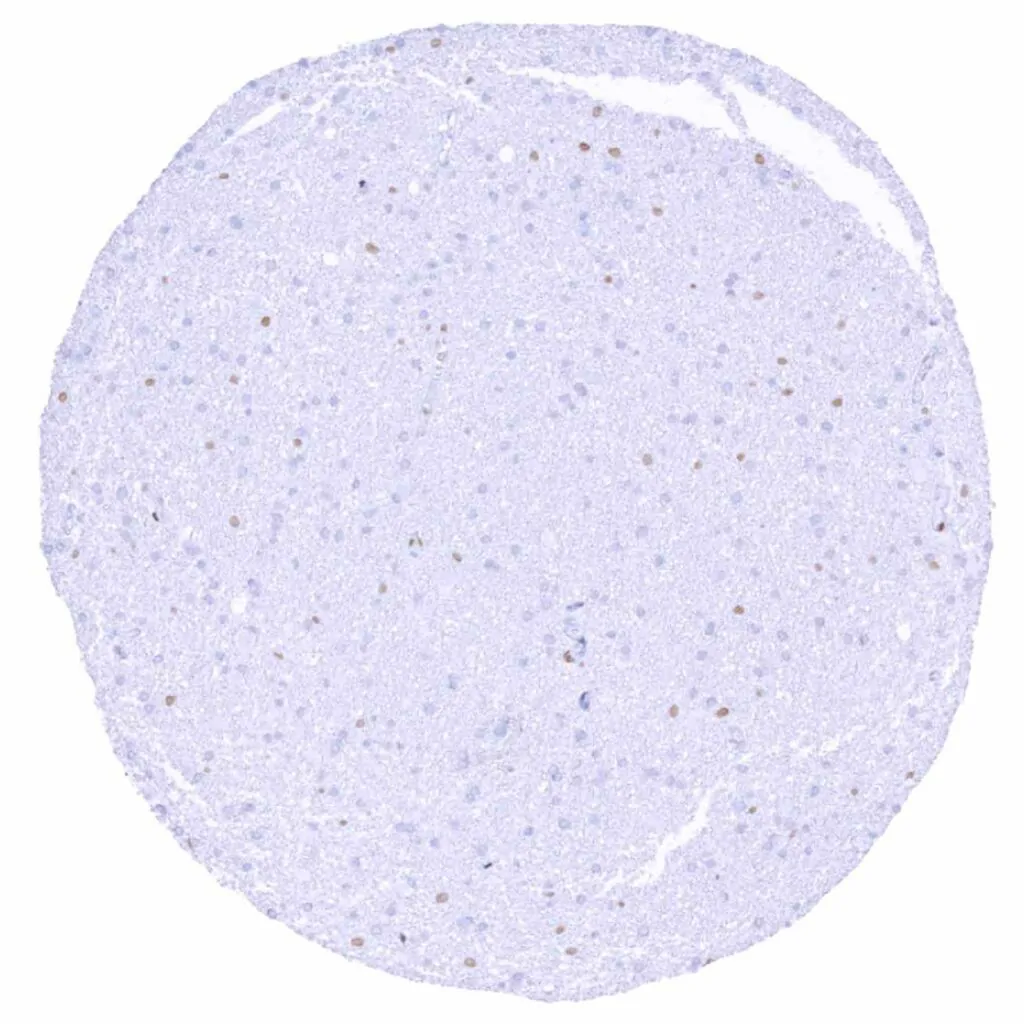

Cerebrum, grey matter – Weak to moderate TLE1 staining of subsets of glial and neuronal cells

Cerebrum, white matter – Weak to moderate TLE1 staining of subsets of glial cells